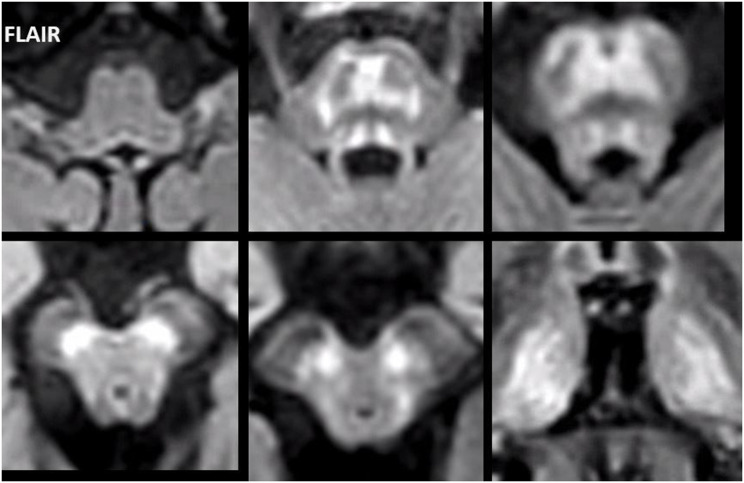

In all adult patients, the first MRI already showed characteristic abnormalities. The typical MRI pattern consisted of symmetric T2 hyperintense signal abnormalities in the thalami, midbrain and pons (Fig. 2). The thalami were affected in eight of the nine patients. The midbrain was affected in all nine adult patients, including T2 hyperintensity of the substantia nigra in all patients and superior colliculi in seven patients. The grey matter of the pons was selectively involved in eight patients, sparing the corticospinal tracts as well as the ascending sensory tracts. This created either a trident-like configuration or a closed omega (ɷ) (Fig. 3), which was noted in four and two patients, respectively.

The medulla oblongata, middle cerebellar peduncles and cerebellar white matter showed no signal changes. Normally, the T2 signal of the dentate nucleus and the red nucleus is in general lower than the adjacent white matter in adults over 40 years of age. This was the case in none of our adult patients. The T2 signal of the dentate nucleus and red nucleus was evidently higher than white matter in three patients and five patients, respectively, and isointense with the surroundings in the other adult patients. The superior cerebellar peduncles exhibited subtly increased T2 signal in four patients.

We have performed a detailed analysis of the brain MRI abnormalities associated with AMACR deficiency. In the adult patients in our cohort the characteristic MRI pattern involved the pons, midbrain and thalami. Interestingly, we found that the structures involved in the brain stem are grey matter structures with sparing of the major white matter tracts, i.e., corticospinal tracts and ascending sensory tracts. This selective vulnerability is easier to appreciate by comparing MR images of patients with MR images of healthy adults acquired with a sequence optimized to discriminate brain stem nuclei [ref. 22]. On the FLAIR and T2-weighted images in most of our patients this grey matter pathology resulted in the pons in either a trident-like hyperintensity or a closed omega (ɷ). A trident-like abnormality in the pons can also be recognized in patients with osmotic demyelination syndrome [ref. 23], although in those cases it usually is more voluminous than in patients with an AMACR deficiency. Although MRI abnormalities in adults with AMACR deficiency have been described before [ref. 11], the pattern of selective grey matter vulnerability has not been appreciated previously. Recognition of this typical pattern facilitates prompt diagnosis. This is supported by the finding that all adults in our cohort showed characteristic MRI abnormalities at presentation and the majority was diagnosed after recognition of the typical pattern. The abnormalities involving the dentate nucleus, red nucleus and connecting dentatorubral tracts within the superior cerebellar peduncles, described earlier in a study by Haugarvoll et al. [ref. 11], are recognizable in part of our patient group. The signal changes in the dentate nucleus and superior cerebellar peduncles are generally less pronounced or more subtle than those in the pons, midbrain and thalamus. Since none of the children in our cohort showed MRI abnormalities at diagnosis or follow-up, it is unknown whether the neurological symptoms seen in the adult patients are preceded by MRI abnormalities and, if so, by how long. Also, we cannot rule out that the here reported children will have a different course of disease than the adults included in this cohort.